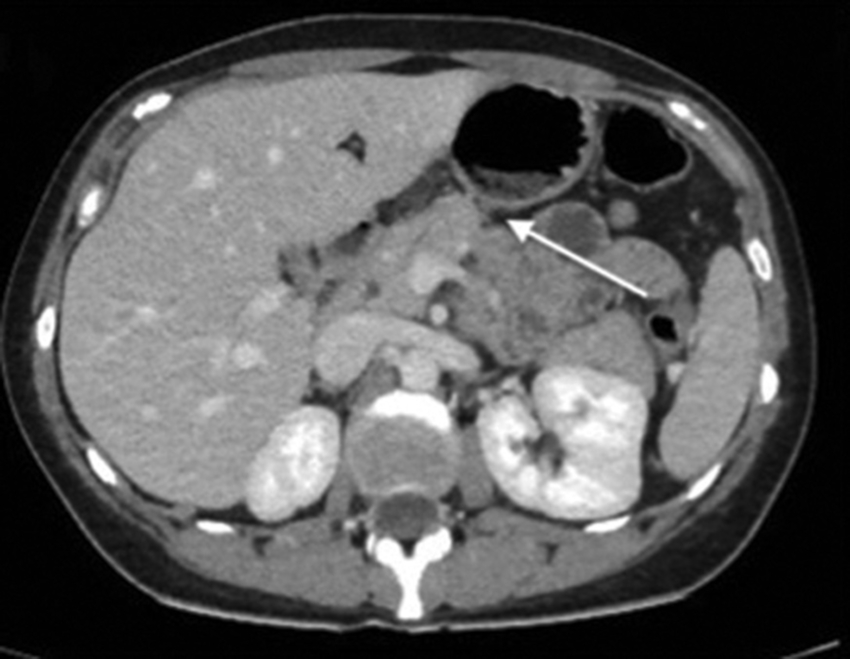

Comunicamos el caso de una mujer de 29 años, sin antecedentes mórbidos de importancia, que consultó por un cuadro de 24 horas de evolución de distensión abdominal y dolor epigástrico, que luego se hizo difuso, sin fiebre. Al examen físico destacaba dolor a la palpación abdominal, preferentemente en el hemiabdomen superior. Se le realizaron exámenes de laboratorio en los que solo se objetivó elevación de la proteína C reactiva con un valor de 14,3 nmol/l. Se decidió estudiar el dolor abdominal con una ecografía, en la que se identificó un área de tejido ecogénico lobulado, relativamente bien delimitado, situado entre el páncreas y la cara posterior del cuerpo y del antro gástrico (Fig. 1), compatible con un proceso inflamatorio del tejido adiposo peripancreático cuya etiología no se precisó. Ante estos hallazgos, se decidió complementar el estudio con una tomografía computada (TC) de abdomen y pelvis con contraste, en la que se confirmó la presencia de un aumento de la densidad del tejido adiposo comprendido entre el páncreas y el estómago, específicamente adyacente a la curvatura menor del estómago y pared posterior (Figs. 2 y 3). El tejido adiposo en relación con la mayor parte de la curvatura mayor presentaba densidad normal. Ante estos hallazgos, se diagnosticó un infarto del epiplón menor, sin signos de complicación, por lo que se decidió manejo con analgesia y controles seriados. La paciente tuvo una evolución favorable con un control a los dos meses con una nueva TC de abdomen y pelvis con contraste, en la que se observó una marcada disminución del aumento de volumen y densidad del omento menor en comparación al examen previo (Fig. 4).